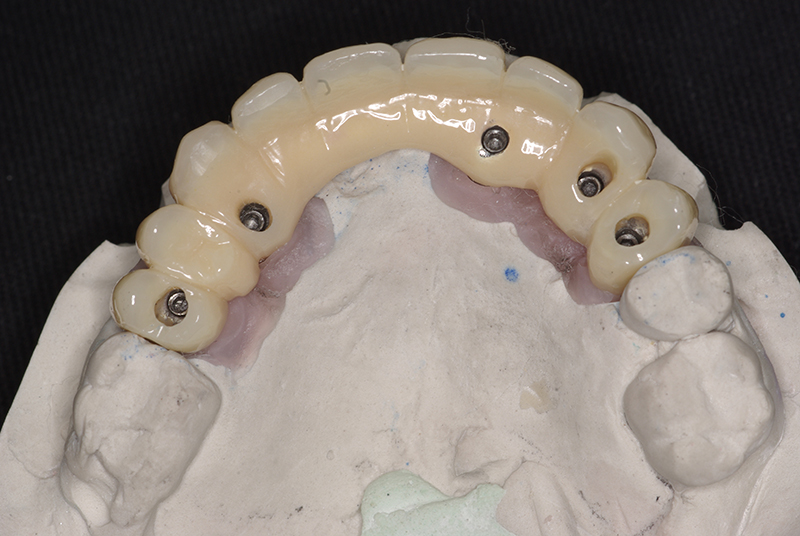

Utilizamos a tecnologia CAD CAM, um sistema avançado que possibilita a confecção precisa das próteses dentárias diretamente sobre os implantes. Esse método inovador garante um ajuste perfeito, um resultado estético superior e proporciona muito mais conforto e durabilidade. Com o CAD CAM, nossos pacientes contam com um processo mais rápido e previsível para alcançar o sorriso desejado.